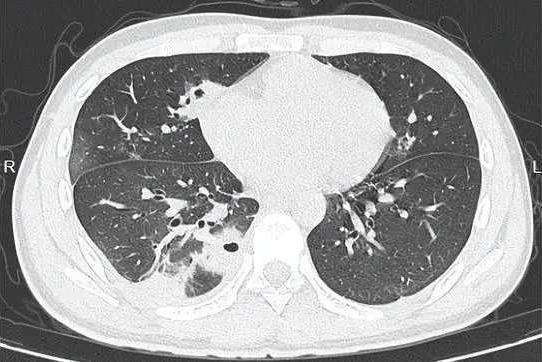

挤一颗痘痘竟致肺里现十几个空洞!大二学生的惨痛教训 20岁的大二学生小林为备考熬夜后,脸部冒出一颗黄豆大小的红肿痘痘。因觉得影响美观,他未洗手便对着镜子将其挤掉,当时看着脓水流出还倍感清爽。 然而几天后,痘痘不仅持续化脓,小林还出现发烧、咳嗽、咳痰等症状,退烧药仅能暂时缓解不适,右下胸更是传来针刺般的疼痛,深呼吸、咳嗽时疼得直冒冷汗。熬至第三天,体温升至39℃的小林紧急前往宁波大学附属第一医院就诊。 接诊的丁群力主任医师通过CT检查发现,小林肺内出现十几个空洞,部分肺组织已坏死,确诊为血源性肺脓肿。细菌培养和基因检测显示,其血液中检出的金黄色葡萄球菌是“元凶”——该细菌原本存在于皮肤表面,而小林挤的痘痘位于脸部“危险三角区”,未洗手的操作让细菌在挤压压力下进入血管引发败血症,进而随血流侵入肺部,侵蚀肺组织导致严重感染。医生提醒,脸部危险三角区的痘痘切勿随意挤压,皮肤出现感染需及时科学处理,避免引发致命风险。